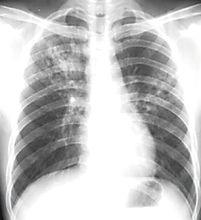

病變的肺

病變的肺內臟反位是一種少見的先天性畸形,有全內臟反位和部分內臟反位兩種類型。